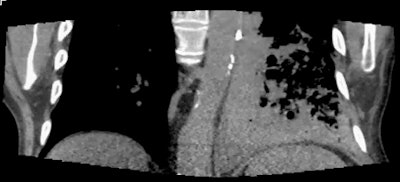

| In a patient with a left lower adenocarcinoma, conventional staging CT was unable to exclude invasion of the left lateral aspect of the aorta. However, static images (one at extreme inspiration and one at extreme expiration, above) and two coronal video files (below) confirm differential motion, and the tumor was confirmed at surgery. Images and cine clips courtesy of Dr. John Troupis. |